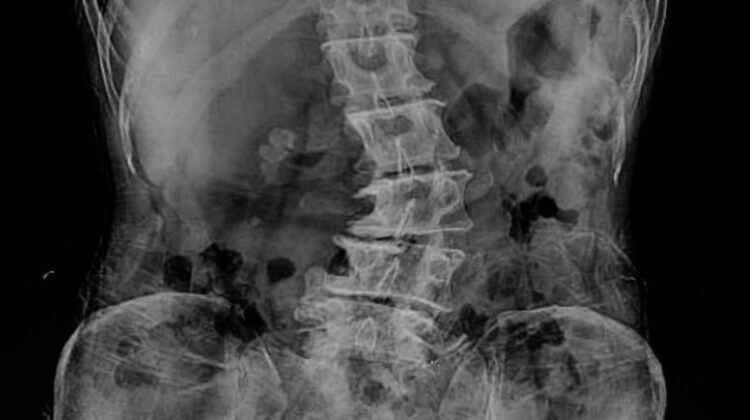

الأشعة السينية (X-ray): لتحديد درجة الانحناء وشكله.

التصوير بالرنين المغناطيسي (MRI): للكشف عن مشاكل الأعصاب أو انزلاق الأقراص.